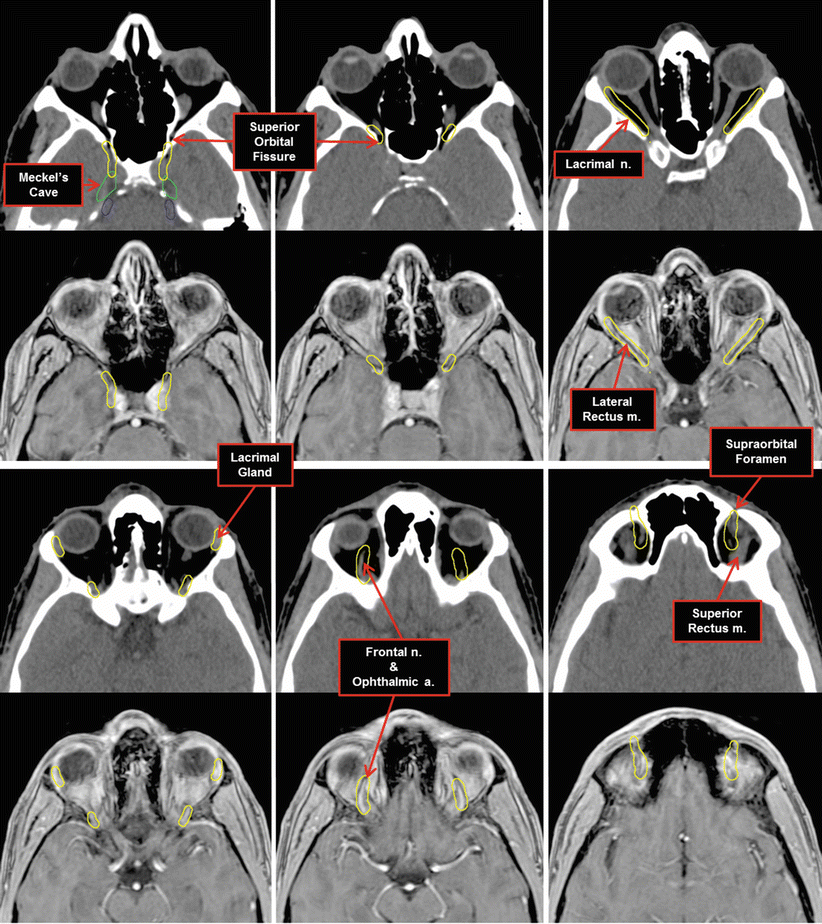

16 Skull Base and Cranial Nerves Radiology Key Optic Nerve Course Radiology Normal optic nerve (white concave arrow) is seen surrounded by perioptic fluid in the optic sheath. Tions along the course of the optic nerve were obtained for the first 100 patients. They categorized pneumatization around optic nerve into 5 types. Ct analysis of optic nerve position and paranasal sinus pneumatization pattern. Optic nerve meningiomas are benign tumors arising from the. Optic Nerve Course Radiology.

Nerves Radiology Key Optic Nerve Course Radiology Normal optic nerve (white concave arrow) is seen surrounded by perioptic fluid in the optic sheath. Tions along the course of the optic nerve were obtained for the first 100 patients. Optic nerve meningiomas are benign tumors arising from the arachnoid cap cells of the optic nerve sheath and represent. This study seeks a case definition of optic nerve tortuosity. Optic Nerve Course Radiology.

Nerves Radiology Key Optic Nerve Course Radiology They categorized pneumatization around optic nerve into 5 types. The course of the intraorbital part of the optic nerve, as demonstrated on anatomic sections in various. Tions along the course of the optic nerve were obtained for the first 100 patients. Optic nerve meningiomas are benign tumors arising from the arachnoid cap cells of the optic nerve sheath and represent.. Optic Nerve Course Radiology.